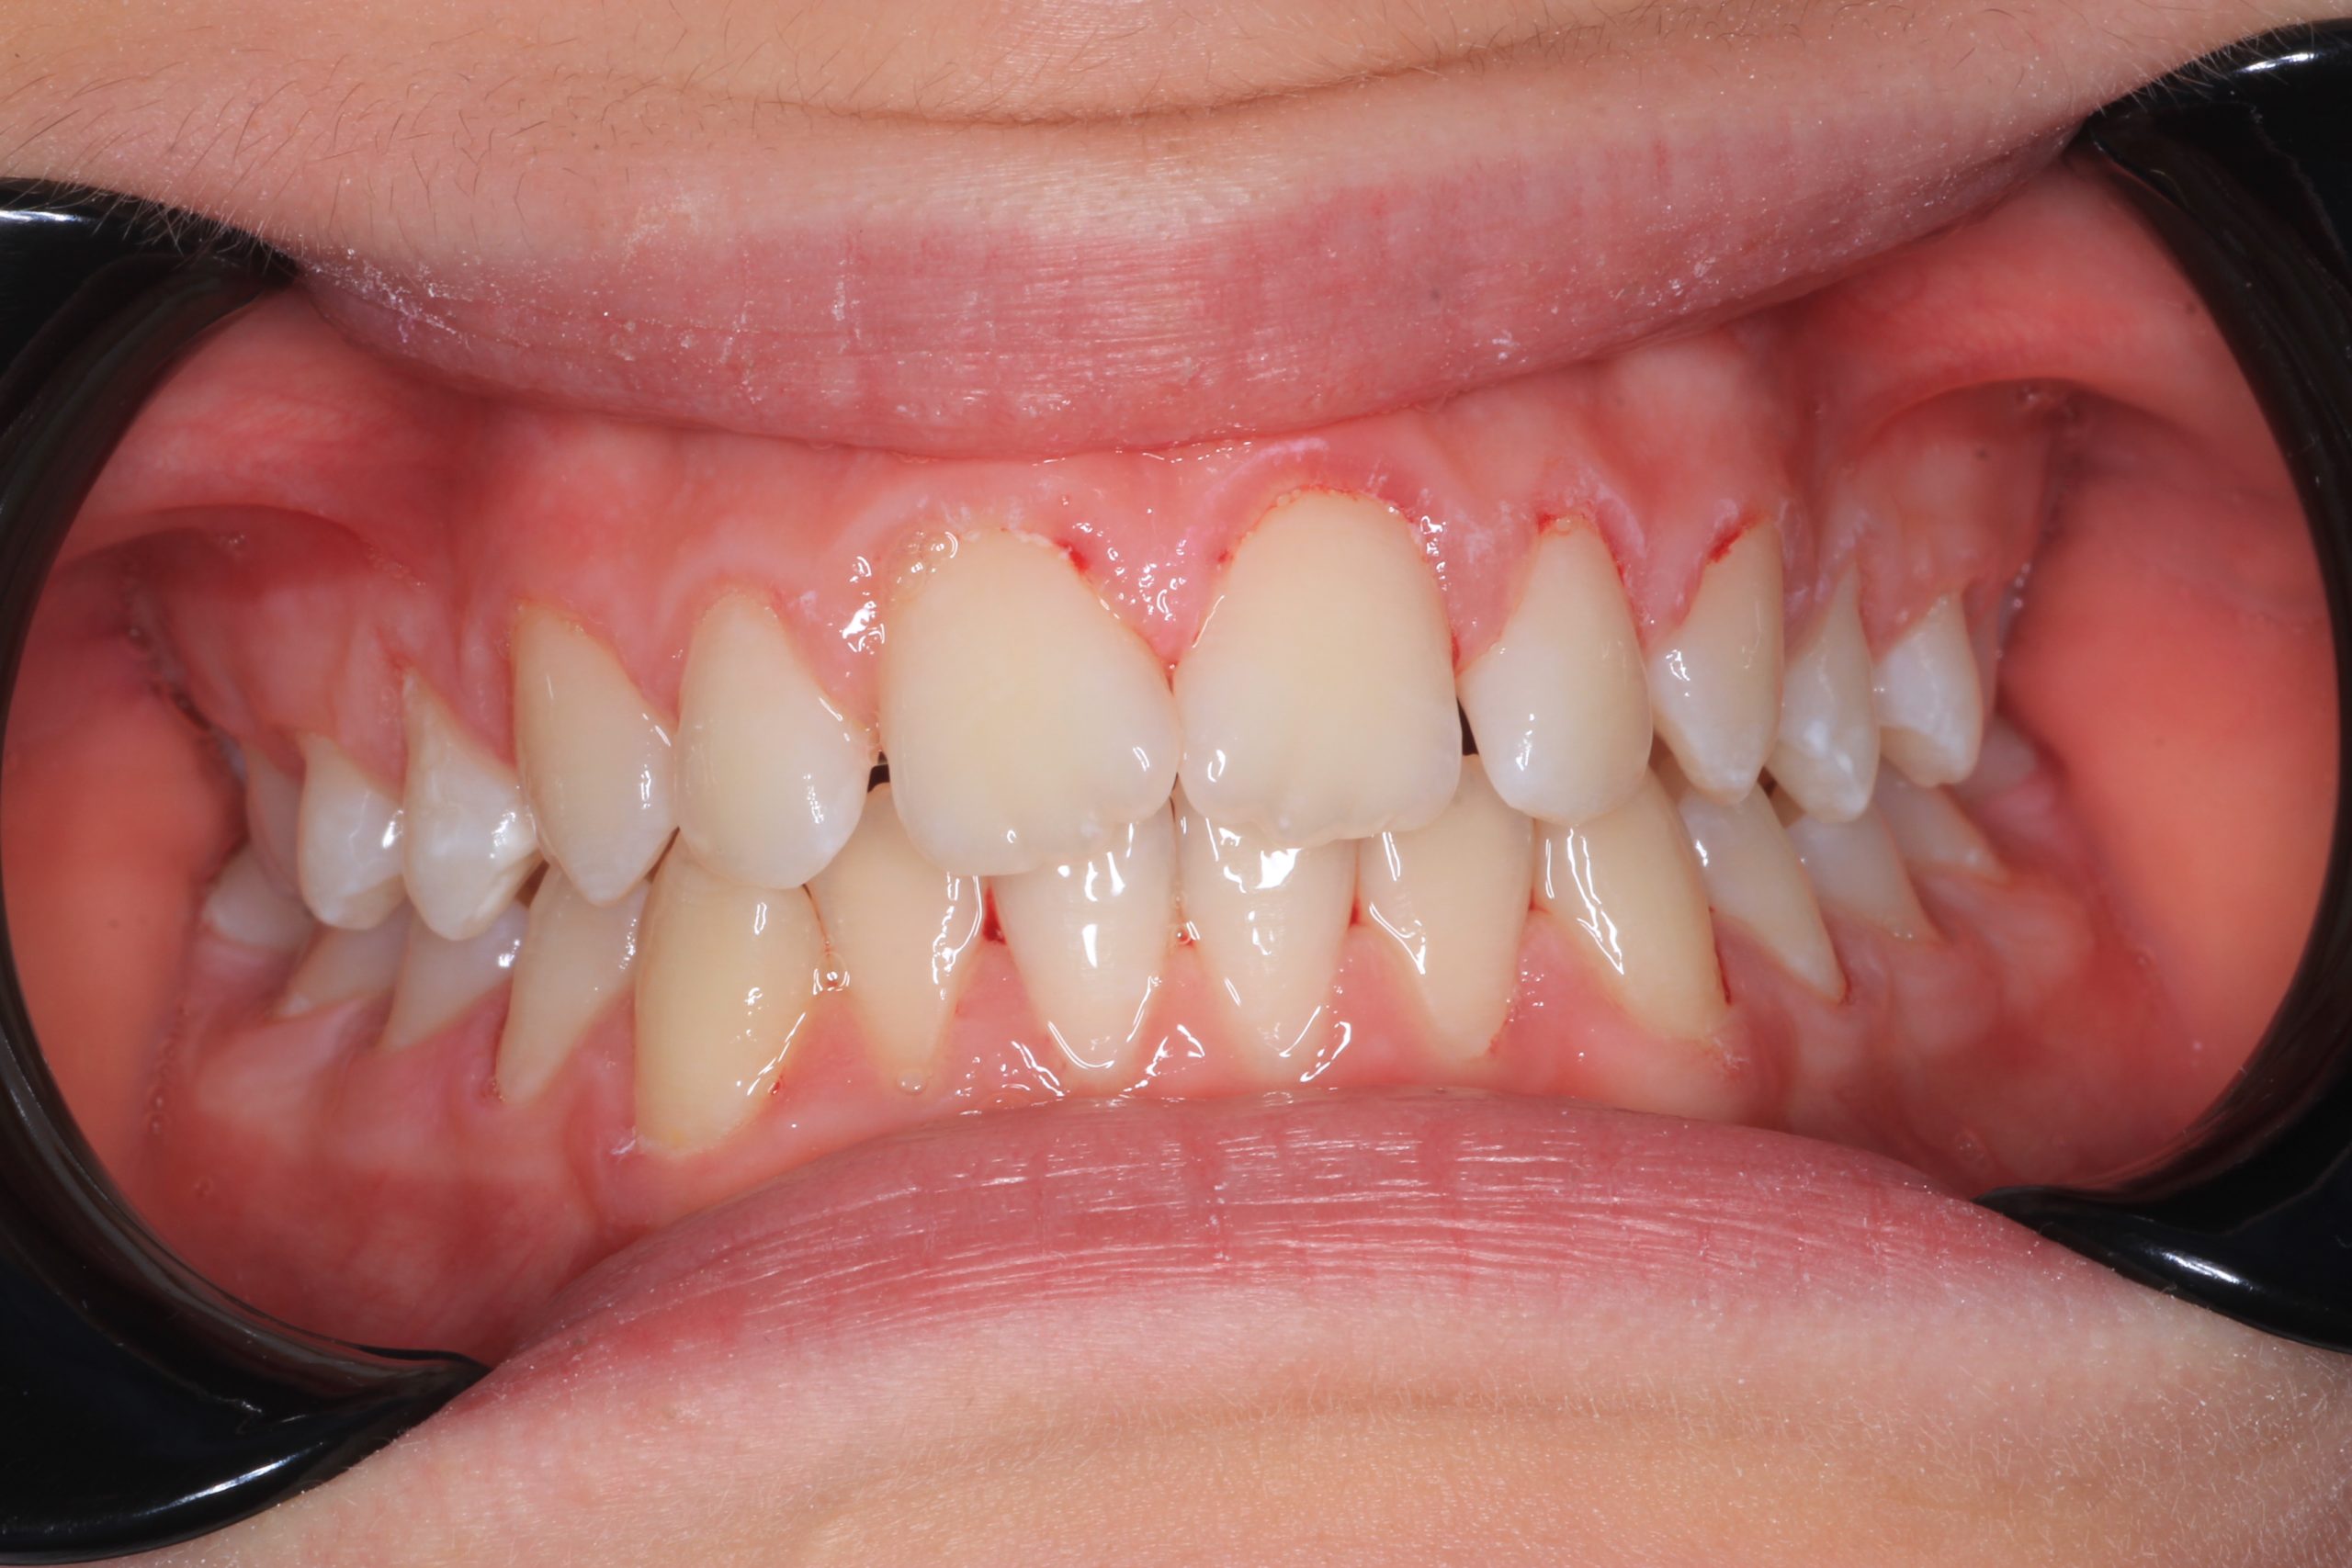

- Detailed Examination

We examine the condition of teeth, gums, and bite. - Plaque Disclosure with Special Indicators